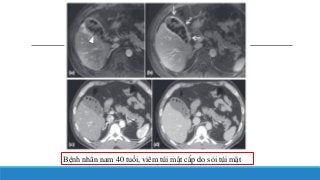

Bệnh nhân nam40 tuổi, viêm túi mật cấp do sỏi túi mật

Hình ảnh VTMcấp trên MRI Pha sớm (a) và pha tĩnh mạch cửa (b) của MRI có cản quang. Pha sớm (c) và pha tĩnh mạch cửa (d) của CT có cản quang. Một vài dấu hiệu thấy được trên hình như + Đầu mũi tên (hình a) chỉ sỏi mật + Thành túi mật bắt thuốc cản quang rõ ( hình b) Thành túi mật, sỏi túi mật hiển diện trên MRI rõ và dễ quan sát hơn CT Đối với đánh giá sỏi MRI mode T2 là hữu ích nhất.